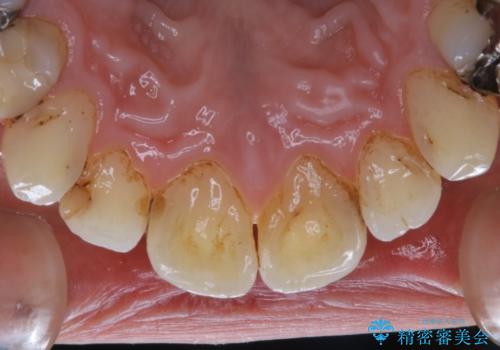

また、治療が開始される前などにも、全体的にクリーニングを行いご自身本来の歯の色、状態を精密に確認することが大切です。